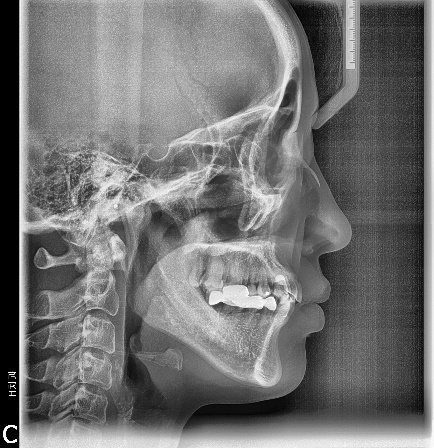

상악에서 miniscrew를 이용한 2mm 정도의 total arch distalization을 계획하였으므로 상응하는 최종교합형성을 고려하여 하악 대구치부에 임플란트식립을 진행하였고 구치부 support의 조기확립을 위해 temporary crown을 이용한 임플란트 상부보철 진행후 하악치열의 후방이동을 진행하기로 하였습니다.

하악임플란트상부보철물에 tube를 부착하되 tube slot에 각형호선이 가급적 passive 하게 들어가도록 보철물의 모양과 tube 부착위치를 조절하였습니다. 계획된 후방이동량만큼 임플란트 보철물과 전방 자연치간의 space를 형성하여 전방치열을 후방견인하였습니다.

마무리된 교합은 초진시에 동일하게 양측 Class 1 교합으로 마무리하였으며 측모두 부방사선 사진에서 보듯 교정중 발생했던 전치의 flare가 개선되었습니다.